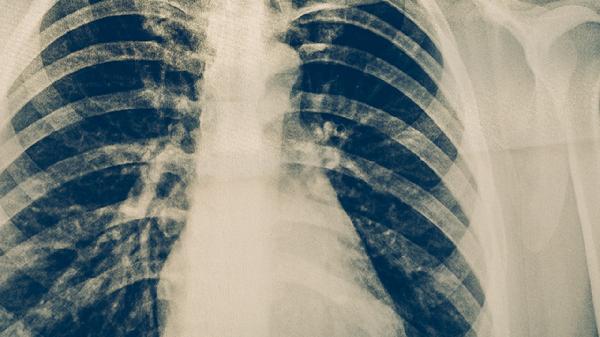

結(jié)核菌素試驗或γ-干擾素釋放試驗陽性者需進(jìn)行胸部X線檢查。高風(fēng)險人群如醫(yī)務(wù)工作者、矽肺患者等應(yīng)每6-12個月篩查一次。長期使用免疫抑制劑者需在用藥前完成結(jié)核感染篩查。接觸過結(jié)核患者的密切接觸者,應(yīng)在暴露后8-10周完成追蹤檢測。